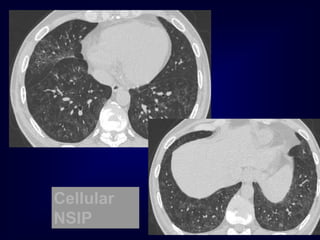

Defining features of Nonspecific Interstitial Pneumonia

(NSIP)

• Clinical: chronic indolent

• Pathology: uniform fibrosis

• Imaging: ground glass + distortion

DI

P

Cellular

NSIP

NSIP: initial reportsof CT spectrum of findings: • Ground glass opacification with or without areas of consolidation • Linear opacities and reticular pattern, but honeycombing limited or absent • Lower zone predominance, may be subpleural predilection Park et al Radiology 1995;195:645 Hartman et al Radiology 2000;217:701

NSIP A fibrosing lungdisease in which ground glass is predominant and honeycombing is minimal or absent, often with a peripheral basal distribution

The Many ‘HRCTFaces’ of NSIP Honeycombing not a prominent feature !!!!